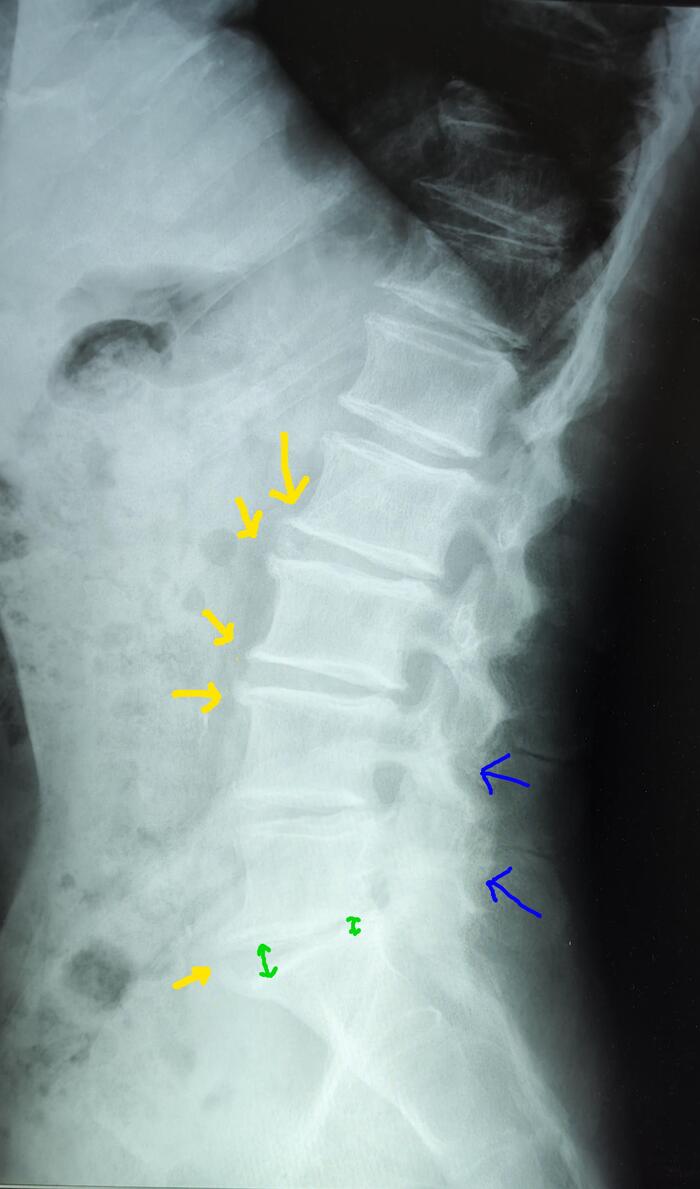

На Р-грамме грудного отдела позвоночника(стоя) в боковой проекции, визуализируется гиперкифоз грудного отдела позвоночника 4 ст. по Коббу. Аналогично с данными МРТ , снижение высоты передних отделов тел Th6,7,8 позвонков(клиновидная деформация).

На МРТ- снижение высоты передних отделов тел Th6,7,8 позвонков(клиновидная деформация).